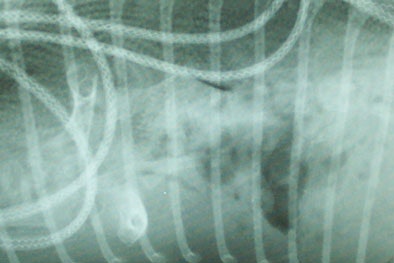

| Above and below: x-ray images show the tangle of the blanket's wiring extending through about 8 feet of a python's digestive tract. The surgery to remove it required an 18-inch incision. All images courtesy of St. Francis Pet Center. |